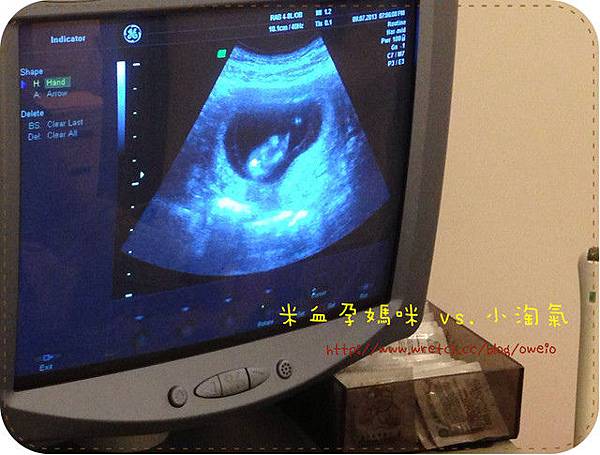

之前看到的小淘氣都只是一團白白的東東,這次好明顯地看到一個"人"的形狀!!!![]()

王院長還用電腦指著說:這是屁股!![]()

可是我根本沒在看王院長到底指的是哪裡,整個沉浸在小淘氣的"人形"裡 ![]()

還照到了小淘氣的頸部透明帶,當王院長一照到這條東西的時候,

我就開始和院長討論起【頸部透明帶】這個東西,稍後再說明。![]()

接著也聽了小淘氣的心跳聲,一樣正常